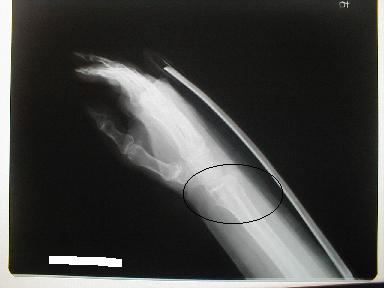

2月25日

3月25日

日常動作には支障なく経過良好にて治癒とする